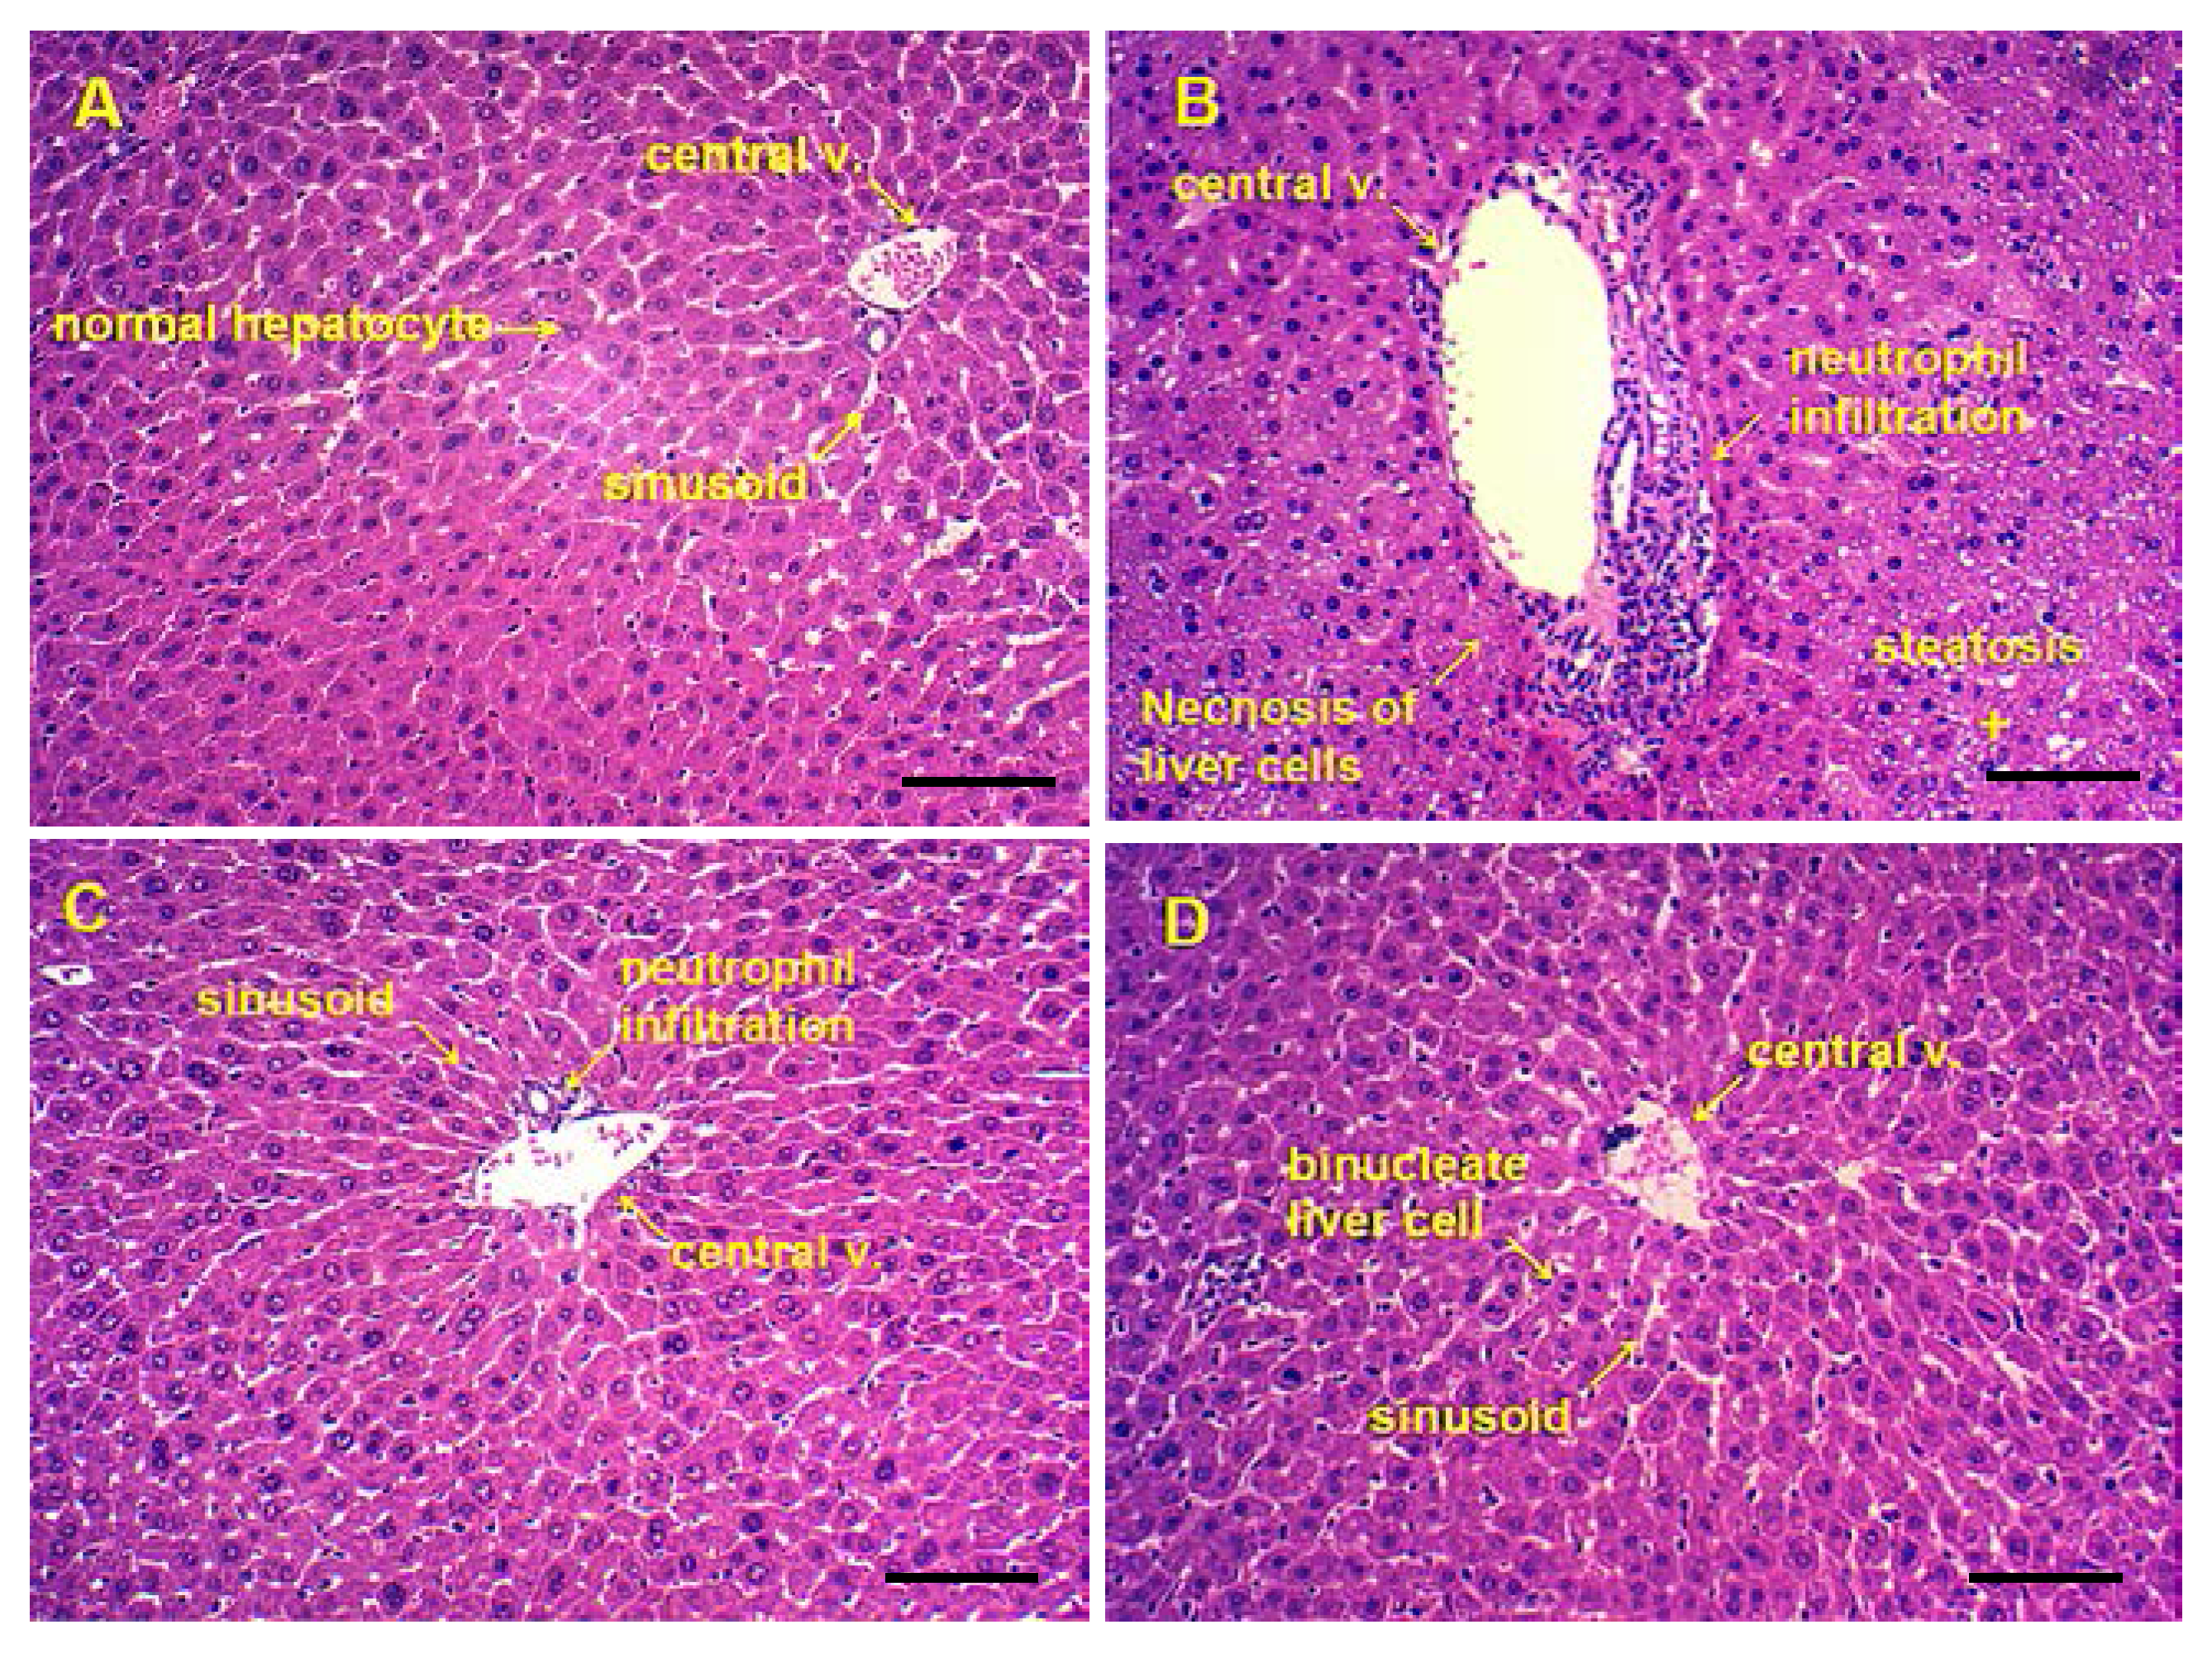

3.6. Pathological Observations and Steatosis Grade

The following figures shows representative photomicrographs of livers obtained from different treatments group. The normal group had clear structure of the hepatic lobule and regular hepatic cords with central veins, the cell nucleus was normal and there was no edema, fatty degeneration or visible lesions (Figure 6A). However, in the alcohol group, typical pathological characteristics, including necrosis, inflammatory infiltration and extensive vacuolar degeneration, confirmed the successful establishment of liver injury (Figure 6B). Pretreatment of Silymarin and maltol exerted a protective effect against alcohol-induced nuclear damage, whereas Silymarin group showed only minor hepatocellular necrosis and infiltration of inflammatory cells (Figure 6C). Treatment with high dose maltol before alcohol exposure noticeably attenuated the apoptotic cells and inflammation, while almost similar to the normal group (Figure 6D). From the results, we speculate that maltol pretreatment might alleviate ethanol-induced liver damage.

Figure 6.

Photomicrographs of liver sections obtained from (A) Normal group, (B) Alcohol group, (C) Alcohol + Silymarin group (Silymarin, 50 mg/kg), and (D) Alcohol + maltol (50 mg/kg) (magnification, all 100×, Bar: 100 μm).